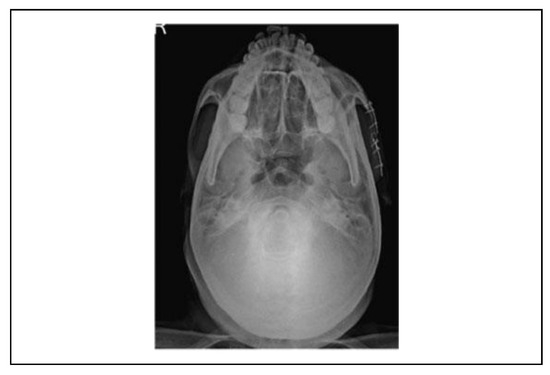

![]() |